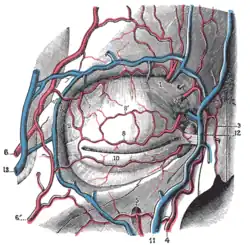

Строение века

Веки защищают переднюю поверхность глаза от неблагоприятного воздействия окружающей среды и способствуют равномерному увлажнению роговицы и конъюнктивы. В веках различают два слоя: поверхностный (передний) — кожно-мышечный, состоящий из кожи и подкожной мышцы, и глубокий (задний) — конъюнктивально-хрящевой, состоящий из хряща и конъюнктивы, покрывающей хрящ сзади. Граница между этими двумя слоями видна на свободном крае века в виде сероватой линии, расположенной впереди многочисленных отверстий мейбомиевых желёз (железы хряща век).

Передний слой верхнего и нижнего века содержит ресницы, близ корней которых заложены сальные железы (железы Цейса).

На краю верхнего и нижнего века у внутреннего угла глазной щели находятся слёзные точки, являющиеся началом слёзных канальцев.